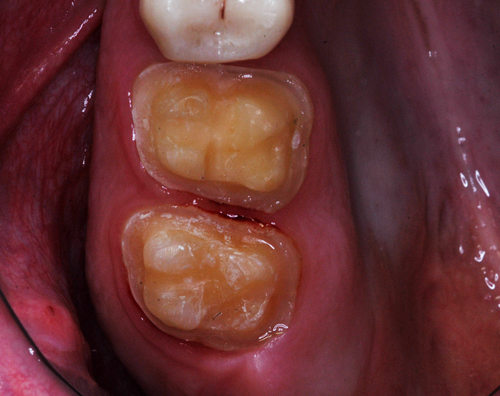

REHABILITACION ORAL MEDIANTE CORONAS DE PORCELANA DE ALTA DENSIDAD Protocolo D.A.T.O. CASO CLINICO: Paciente 24 años, bruxómano, atresia maxilar, referido por ortodoncista para realizar rehabilitación oclusal . Se observa a la inspección la presencia de una hipoplasia adamantina en todos los dientes anteriores, carencia de Guía Anterior , evidentes signos de Facetas Parafuncionales de Desgaste en los posteriores, y una marcada convergencia de los ejes dentarios ápico oclusal, tanto en el maxilar superior como en el inferior, siendo el superior el mas difícil de resolver dado que la inclinación de la Curva de Wilson es inversa a lo que presenta el enfermo. Radiograficamente sin patologías presentes. No presenta movilidades dentarias ni síntomas articulares en las ATM. Debido a la excesiva contractura de su musculatura, se realiza la relajación obviando el uso corriente de las Laminillas de Long, reemplazando el método por un Jig de Lucia el que se deja en boca desde la noche anterior a la cita, advirtiendo al paciente que no debe quitarlo en ningún momento , ya que de hacerlo se repetirían los engramas musculares anómalos que el enfermo presenta. En esas condiciones se toman registros intermaxilares mediante silicona de registros, y se registra el maxilar superior respecto del plano de Frankfort mediante arco facial estático. Se llevan a cabo los encerados correspondientes y se construye en base a ellos el primer juego de provisionales, los que no son cementados debido al perfecto anclaje que presenta. Transcurridos seis meses del uso de provisionales , durante los cuales se ha observado la Oclusión en Relación Céntrica (ORC) inalterable, la ausencia de desgastes patológicos (en las provisorias) y la ausencia de síntomas articulares y musculares, deducimos que el paciente se mantiene en una orto función adecuada, por lo cual comenzamos su rehabilitación definitiva construyendo su Guía Anterior ( determinante primario de la oclusión) en porcelana sobre porcelana de alta densidad.. Observamos los espacios correspondientes en los sectores posteriores y las Disclusiones de los mismos. Los tallados ha sido realizados mediante el concepto de Tallados Gnatológicos, recreados por el Prof. Alvarez Cantoni bajo la denominación de “Preparaciones Racionales”( PREPARACIONES RACIONALES EN PRÓTESIS PARCIAL FIJA. Ed. Hacheace) probando finalmente el trabajo luego de varios días de cementado provisional, y observando la adaptación periférica del borde cavo superficial , su aspecto estético y el importante factor disclusivo : CURVA DE WILSON. y verificando la eficacia lograda mediante una Oclusión Mutuamente Compartida, en la observación de una Disclusión derecha en el Lado de Trabajo y no Trabajo de una disclusión izquierda como así también en la disclusión propulsiva Utilizamos papel de articular de ocho(8) micras para verificar la eficacia de las disclusiones. y de los puntos interoclusales de contacto ANTES DESPUES

Luego de un par de entrevistas, se le informa acerca de la hipofunción masticatoria evidente, producto de la destrucción no solo de las piezas anteriores, sino también de la paulatina generación de Facetas Parafuncionales de Desgaste que determinan una eficacia masticatoria deficiente.

Facetas estas donde puede observarse el típico fenómeno de “DESGASTE EN OLLA”, constituido por el facetamiento doblemente profundo de las Cúspides Estampadoras respecto de las Cúspides de Corte.